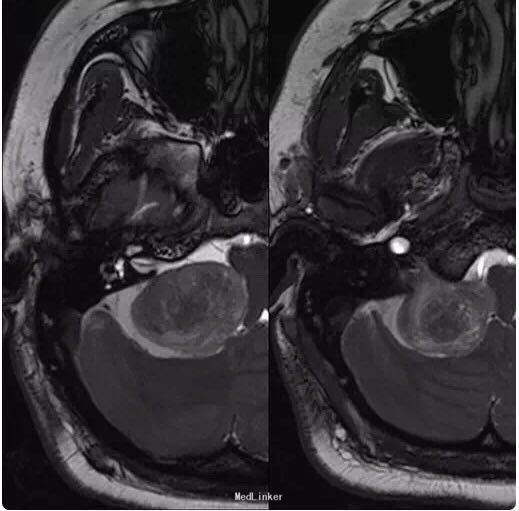

女性患者,34 岁,主因头痛、右耳听力损害以及平衡障碍 3 个月入院。

行头颅影像学检查、轴位 T1 像、轴位增强后 T1 像、冠状位增强后 T1 像以及轴位 T2 像:显示在右侧桥脑小脑角部位有一边界清楚病灶,T1 为低信号,T2 为高信号,并且伴有强化;病灶扩展至右侧颈静脉孔区,导致颈静脉孔增宽,脑干、第四脑室和小脑变形。右侧内耳道正常,病灶无颅外扩展。轴位 T2 加权 GRE 成像显示多发性病灶内出血:

诊断为颈静脉孔区神经鞘瘤。 手术切除辅助以立体定向放疗。